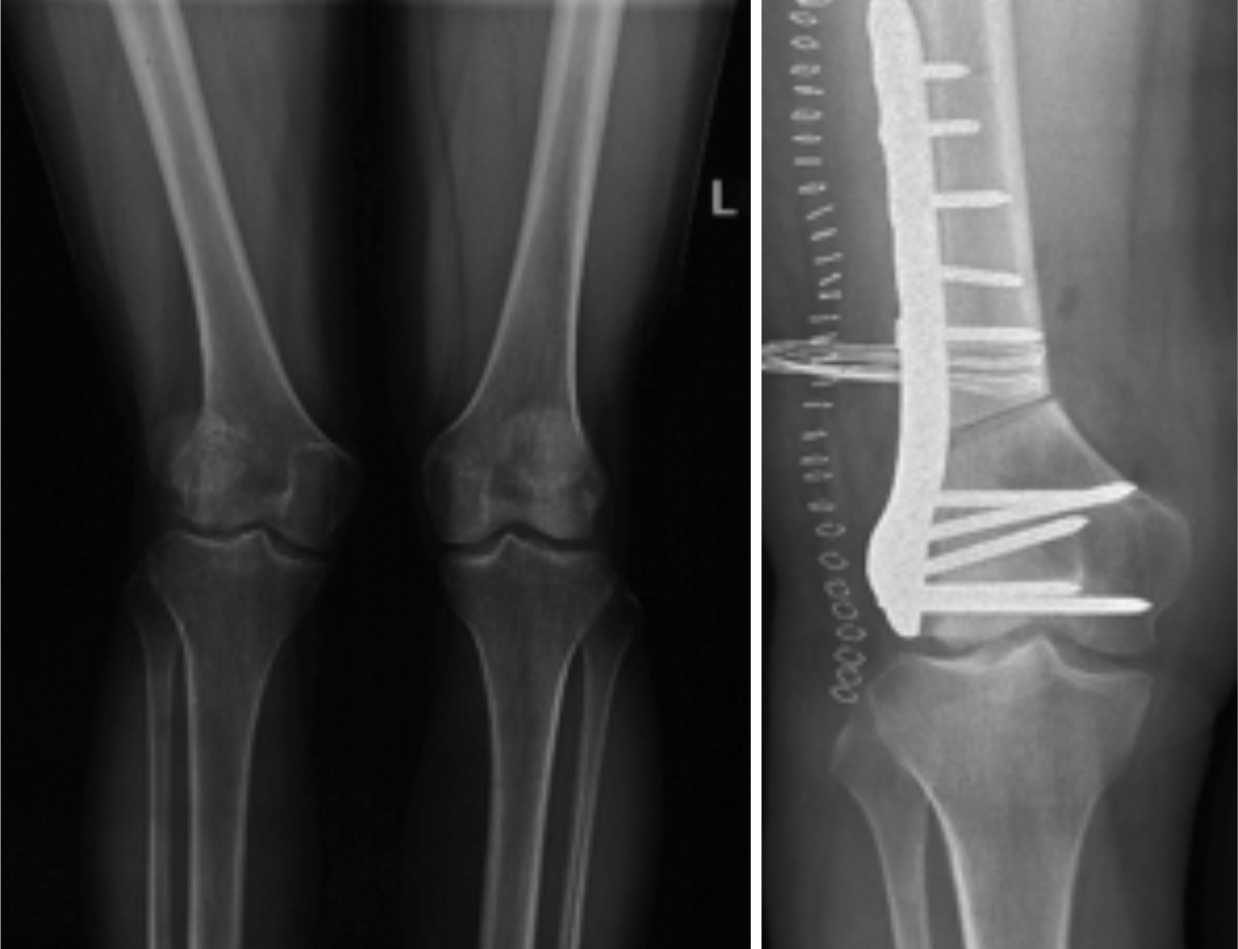

二、截骨矫形

成人肢体骨与软组织畸形、如:斜颈畸形、臀肌筋膜挛缩症、先天性骨关节疾病畸形、先天性髋关节脱位分期治疗、先天性马蹄内翻足矫形术、X型腿、O型腿、创伤后畸形、小儿麻痹后遗症的肢体畸形矫形、脑性瘫后遗症的肢体畸形矫形等。

胫骨截骨矫形手术(HTO)

股骨远端截骨矫正膝外翻